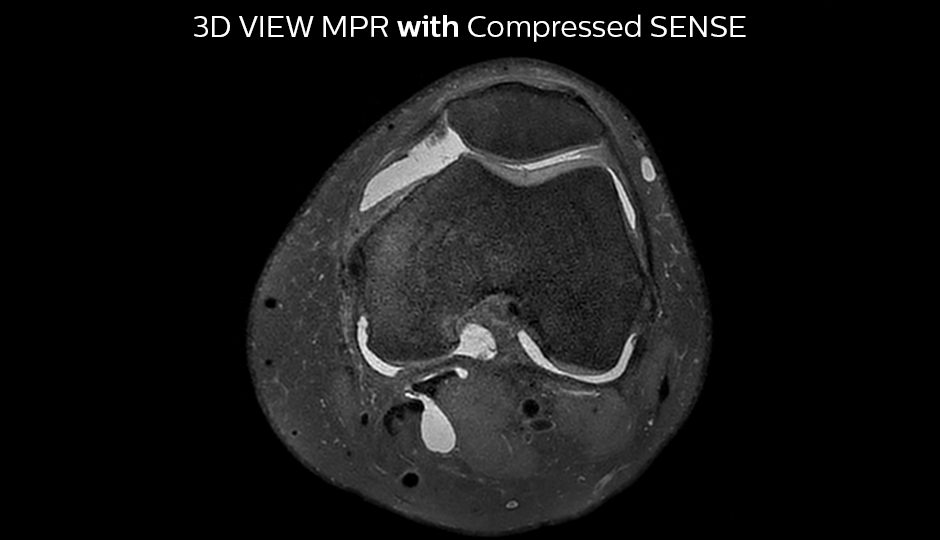

Comparing 2D with 3D using Compressed SENSE

A good acquisition time with high resolution is obtained when moving from three 2D acquisitions in three planes to one 3D acquisition with Compressed SENSE. In this example, Compressed SENSE with 3D VIEW PD SPAIR is 50% faster than three separate 2D scans and has improved spatial resolution.

With Compressed SENSE factor 10

3D VIEW PD SPAIR high resolution knee

Scan time 5:03 min.

Voxel size 0.6 x 0.6 x 0.6 mm